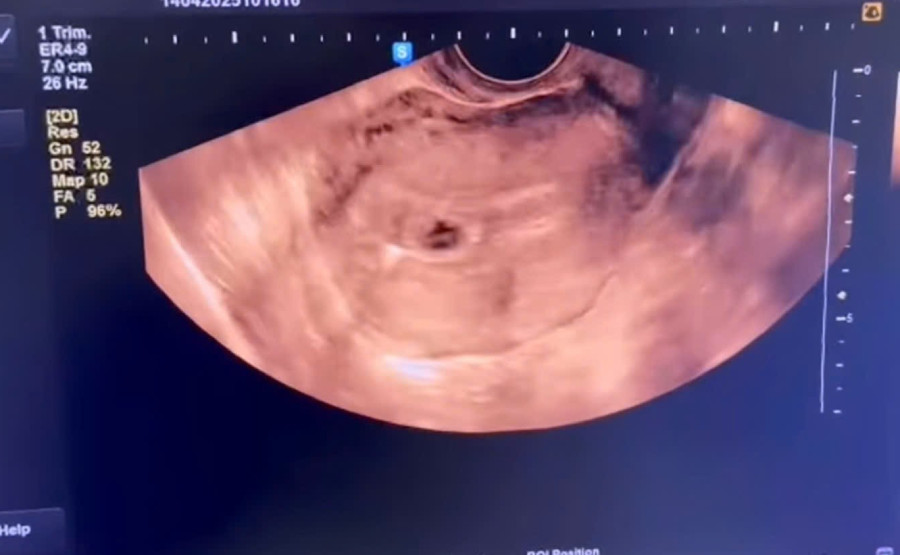

Bốn năm trước, người phụ nữ này đã thực hiện kế hoạch hóa gia đình bằng phương pháp đặt vòng tránh thai. Tại Trung tâm Y tế huyện Thanh Sơn, sau khi thăm khám và siêu âm, kết quả cho thấy tử cung kích thước lớn hơn bình thường, trong buồng tử cung hình ảnh có túi thai, chị được kết luận đang mang thai tuần thứ 4.